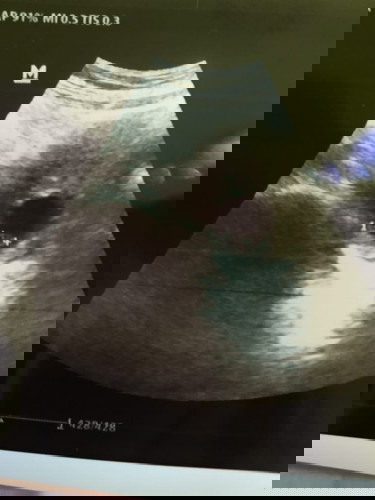

bun saya mau tnya ada gak yg serupa kyak saya. usia kehamilan saya 6w jlan 7w dan tgal 22 usg kantung hamil dan biji janin normal setelah 5hari kantung hamil mengecil dan calon janin tidak kelihatan lagi. itu kenapa ya kira" kalau ada pengalaman serupa gimana ya bun cara perbaiki dan penyebab nya. #bantusharing #jangandibully #Nanya #babyfirst #seriusnanya